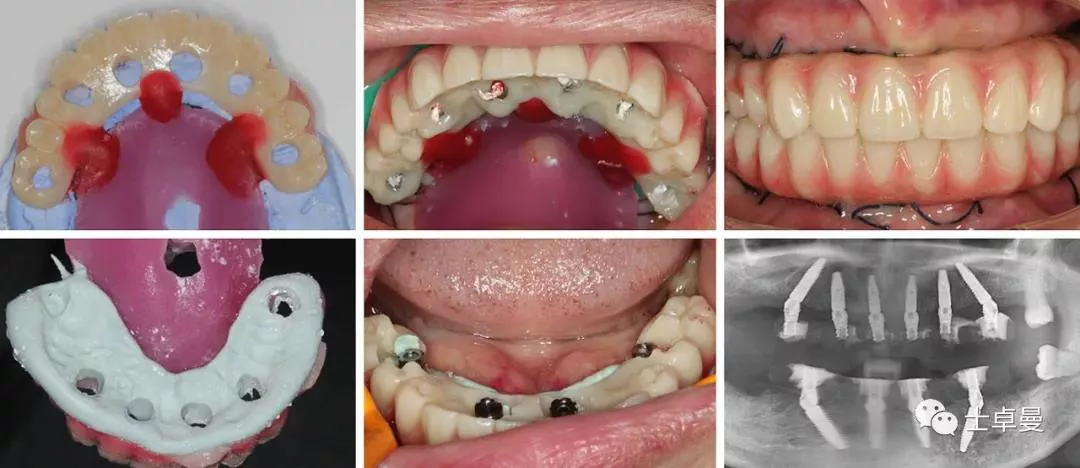

· 常规消毒碧蓝麻局麻下,利用牙支持式导板确定固位钉位置后取下导板;

· 然后分离牙龈,于牙槽嵴颊腭侧略翻瓣暴露牙根与牙槽骨间隙,切除龈瓣边缘炎性肉芽组织,拔除上颌16-27牙,球钻清理拔牙窝,并用大量生理盐水冲洗;

· 通过先前固位钉位置安放固位钉支持式种植导板,因拔牙前后软硬组织变化较大,需耐心寻找先前固位钉位置;

· 导板就位后利用Straumann BLT全程导板工具盒全程备洞,取下导板后利用测量杆确认种植体窝方向和深度以及种植窝周围骨量;

· 植入6颗Straumann BLT种植体,植入扭矩均达到45Ncm以上:

✓ 16、26:4.1mm×14mm

✓ 14、24:4.1mm×12mm

✓ 12、22:3.3mm×12mm

· 安装SRA基台,均加力至35Ncm:

✓ 16、26:RC30°4mmA型

✓ 14,24:RC17°2.5mmA型

✓ 12,22:NC17°2.5mmA型

· 旋入SRA基台保护帽,修整粘膜,缝合。

下颌种植手术

· 手术操作流程与上颌基本一致,最终植入4颗Straumann BLT种植体,植入扭矩均达到45Ncm以上:

✓ 35、45:4.1mm×14mm

✓ 32、42:3.3mm×12mm

✓ 35、45:RC30°4mmA型

✓ 32、42:NC直型2.5mm

· 手术完成后复查CBCT与术前设计对比,验证植入精度。